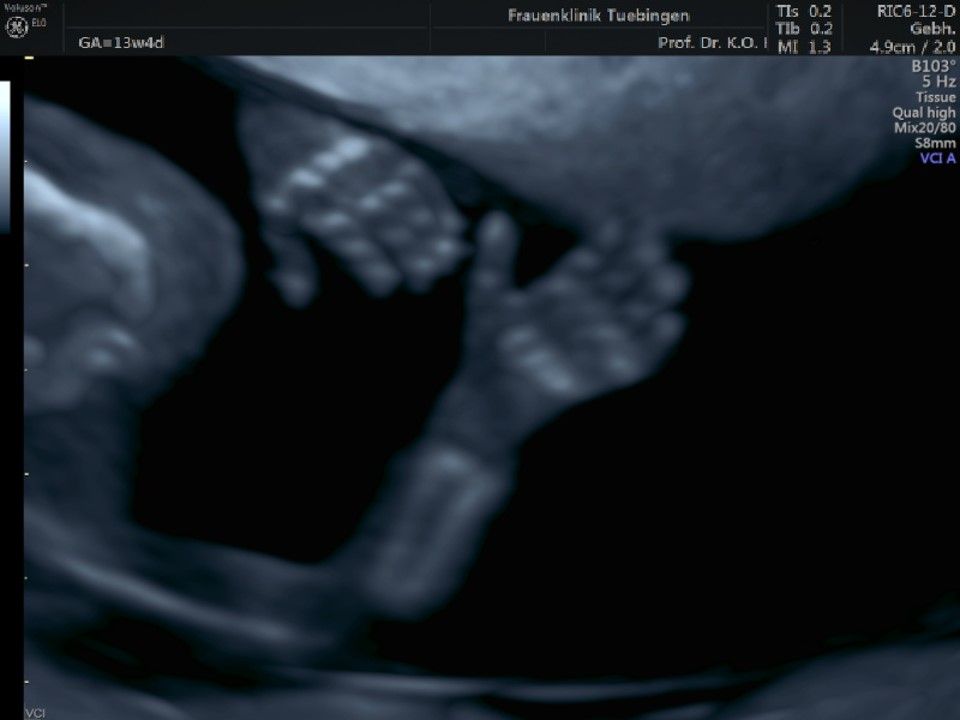

Im Rahmen des Ersttrimester-Screenings untersuchen wir die Organe des Feten mittels Ultraschall. Dabei machen wir auch gerne ein Bild für Sie.

Obwohl der Fet zu diesem Zeitpunkt erst zwischen 5 und 8cm groß ist, lassen sich bereits etwa die Hälfte aller schwerwiegenden Fehlbildungen erkennen bzw. ausschließen. Sollten wir eine Auffälligkeit sehen, werden wir mit Ihnen den Befund und das weitere Vorgehen ausführlich besprechen.